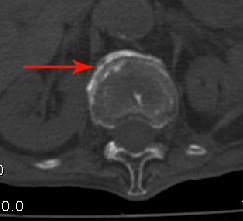

男:89岁因外伤后2天行ct检查。请各位战友讨论图中所指是否是骨折和形成该影像的原因(扫描层面位于椎体中份)。

椎体前缘双边征,其后椎体内密度增高均提示压缩性骨折

老年性骨质疏松,椎体前缘出现双边征支持压缩骨折。椎体骨质稀疏,似有破坏,警惕溶骨性骨转移。

椎体前缘呈双边征 考虑 压缩性骨折,椎体退行性病变。

我的报告1:腰椎骨质退行性改变。

2:t12改变考虑压缩骨折?请结合临床。